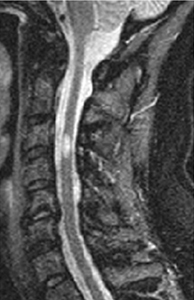

A RNM da medula espinhal é recomendada para todos os pacientes. Muitos pacientes com EM terão lesões da medula espinhal cervical, e a especificidade deste achado é muito alta.[Figure caption and citation for the preceding image starts]: Ressonância nuclear magnética (RNM) da coluna cervical de alto campo (≥1 Tesla) ilustrando uma lesão que pode causar sintomas mielopáticos de disfunção do intestino e da bexiga, bem como paraparesia espásticaDo acervo do Dr. Lael A. Stone [Citation ends].

A medula espinhal cervical e toracolombar, inclusive o cone, deve ser analisada por exame de imagem. Pode ser usado um aparelho de 1.5 T ou 3 T. Recomenda-se o uso de sequências sagitais com realce por gadolínio.[3] A RNM também é usada para avaliar a atividade da doença e monitorar a eficácia do tratamento.[3]

lesões desmielinizantes na medula espinhal, particularmente na medula espinhal cervical; detecção de diagnóstico alternativo, como espondilose cervical